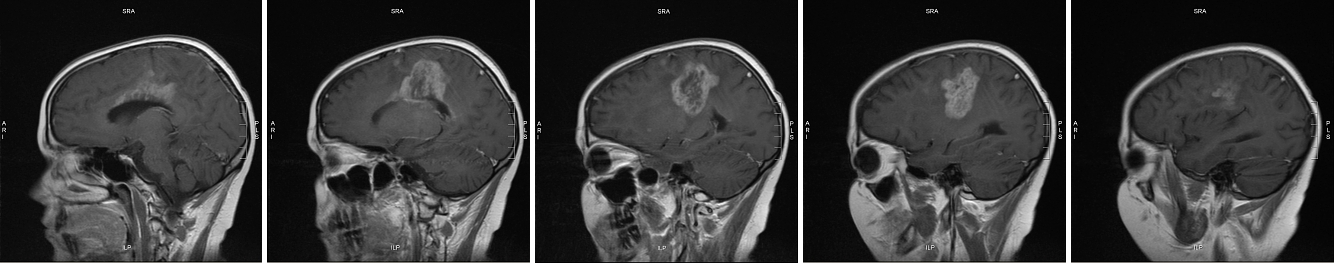

The images below are another view on the growth you see above. The top series is from 10 April 2007; the bottom from 21 May. Each series starts at the midline in the brain (the dividing line between left and right hemispheres) and proceeds out toward Meghan’s left ear. Note that the April scans begin slightly closer to the midline (you can see Meghan’s spinal cord in the first image). This means each April image comes “before” (closer to the midline than) its corresponding May image.

side view May 2007 series side view June 2007 series